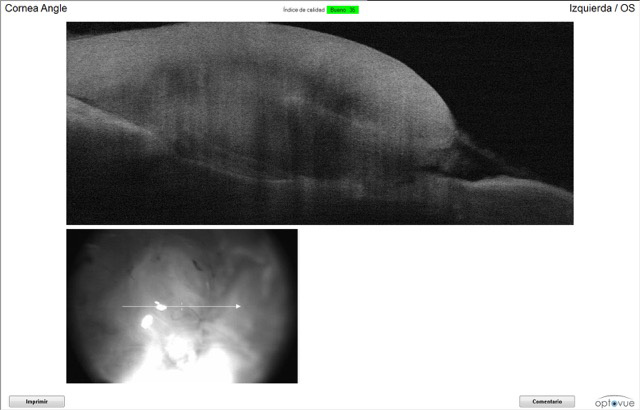

OCT del ojo izquierdo a la semana de la cirugía.

Imágenes OCT del ojo izquierdo de Iker en su segunda revisión. Se aprecia la adherencia a la córnea y la medición del espesor de la córnea.

El test de fluoresceína solo dio positivo en las zonas de los puntos. La OCT nos mostró cómo el injerto y el coágulo cada vez están mas adheridos a la córnea de Iker. La tonometría se le realizó para controlar la hipertensión ocular, y los valores fueron normales. El test Dazzle dió positivo (responde a las luces), tiene reflejos pupilares.